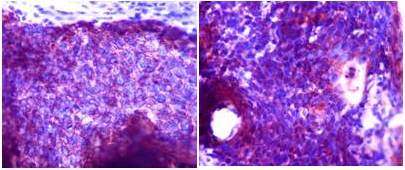

No observan tejido ganglionar linfático remanente, por lo que infieren que los hallazgos son compatibles con neoplasia primaria originaria de un quiste branquial complementando con realización de estudio de inmunohistoquímica, el cual resultó positivo para citoqueratina 34BE12, P63 y citoqueratina 7.